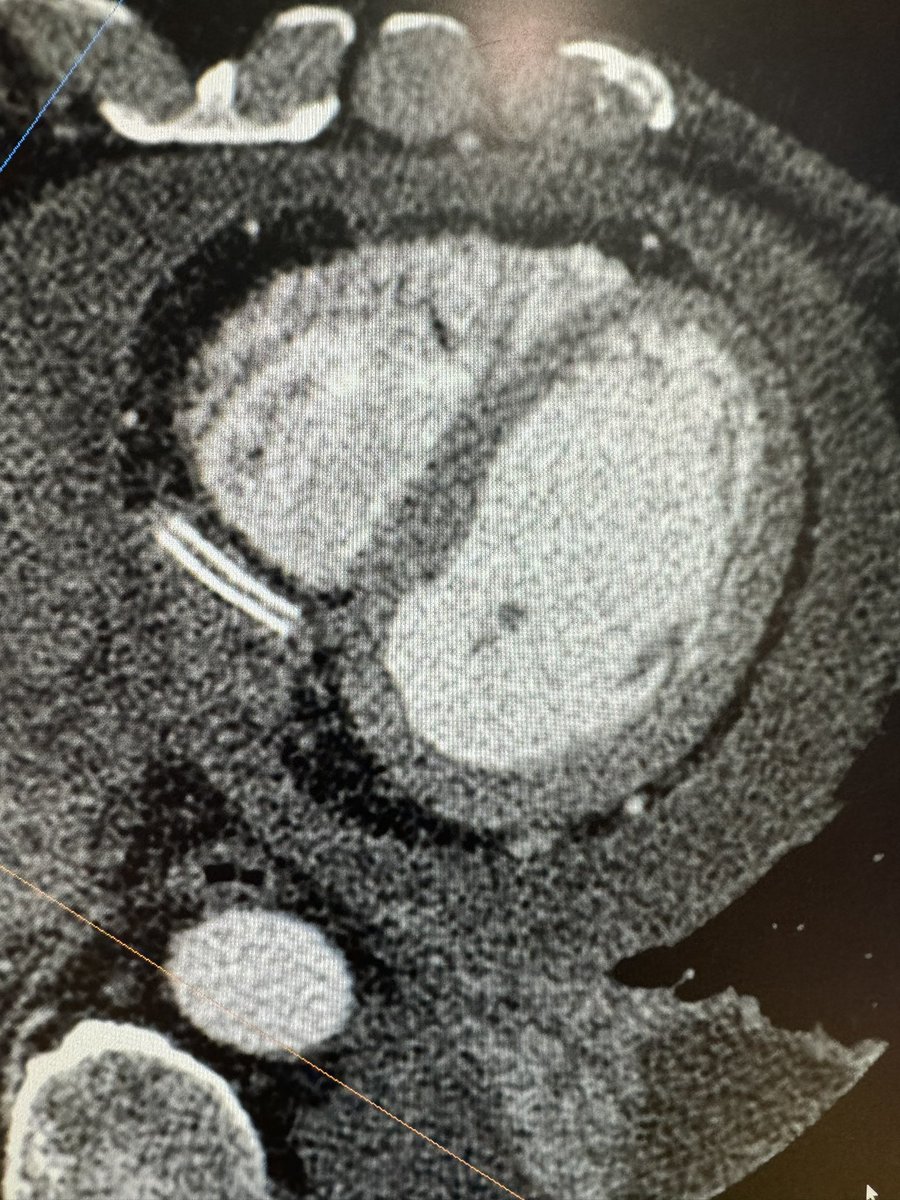

Resource and OUTcome Impact of routiNE availability of Computed Tomography Perfusion #EHJCVI @AndreBaggi @gpontone1 and colleagues ➡️ academic.oup.com/ehjcimaging/ad… @ESC_Journals @bernhard_gerber @JGrapsa @DonalErwan @EACVIPresident